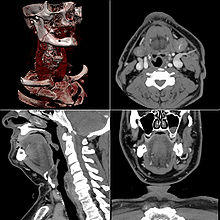

Neck

Contrast CT is generally the initial study of choice for neck masses in adults.[24] CT of the thyroid plays an important role in the evaluation of thyroid cancer.[25] Also, CT scans often incidentally find thyroid abnormalities, and thereby practically becomes the first investigation modality.[25]